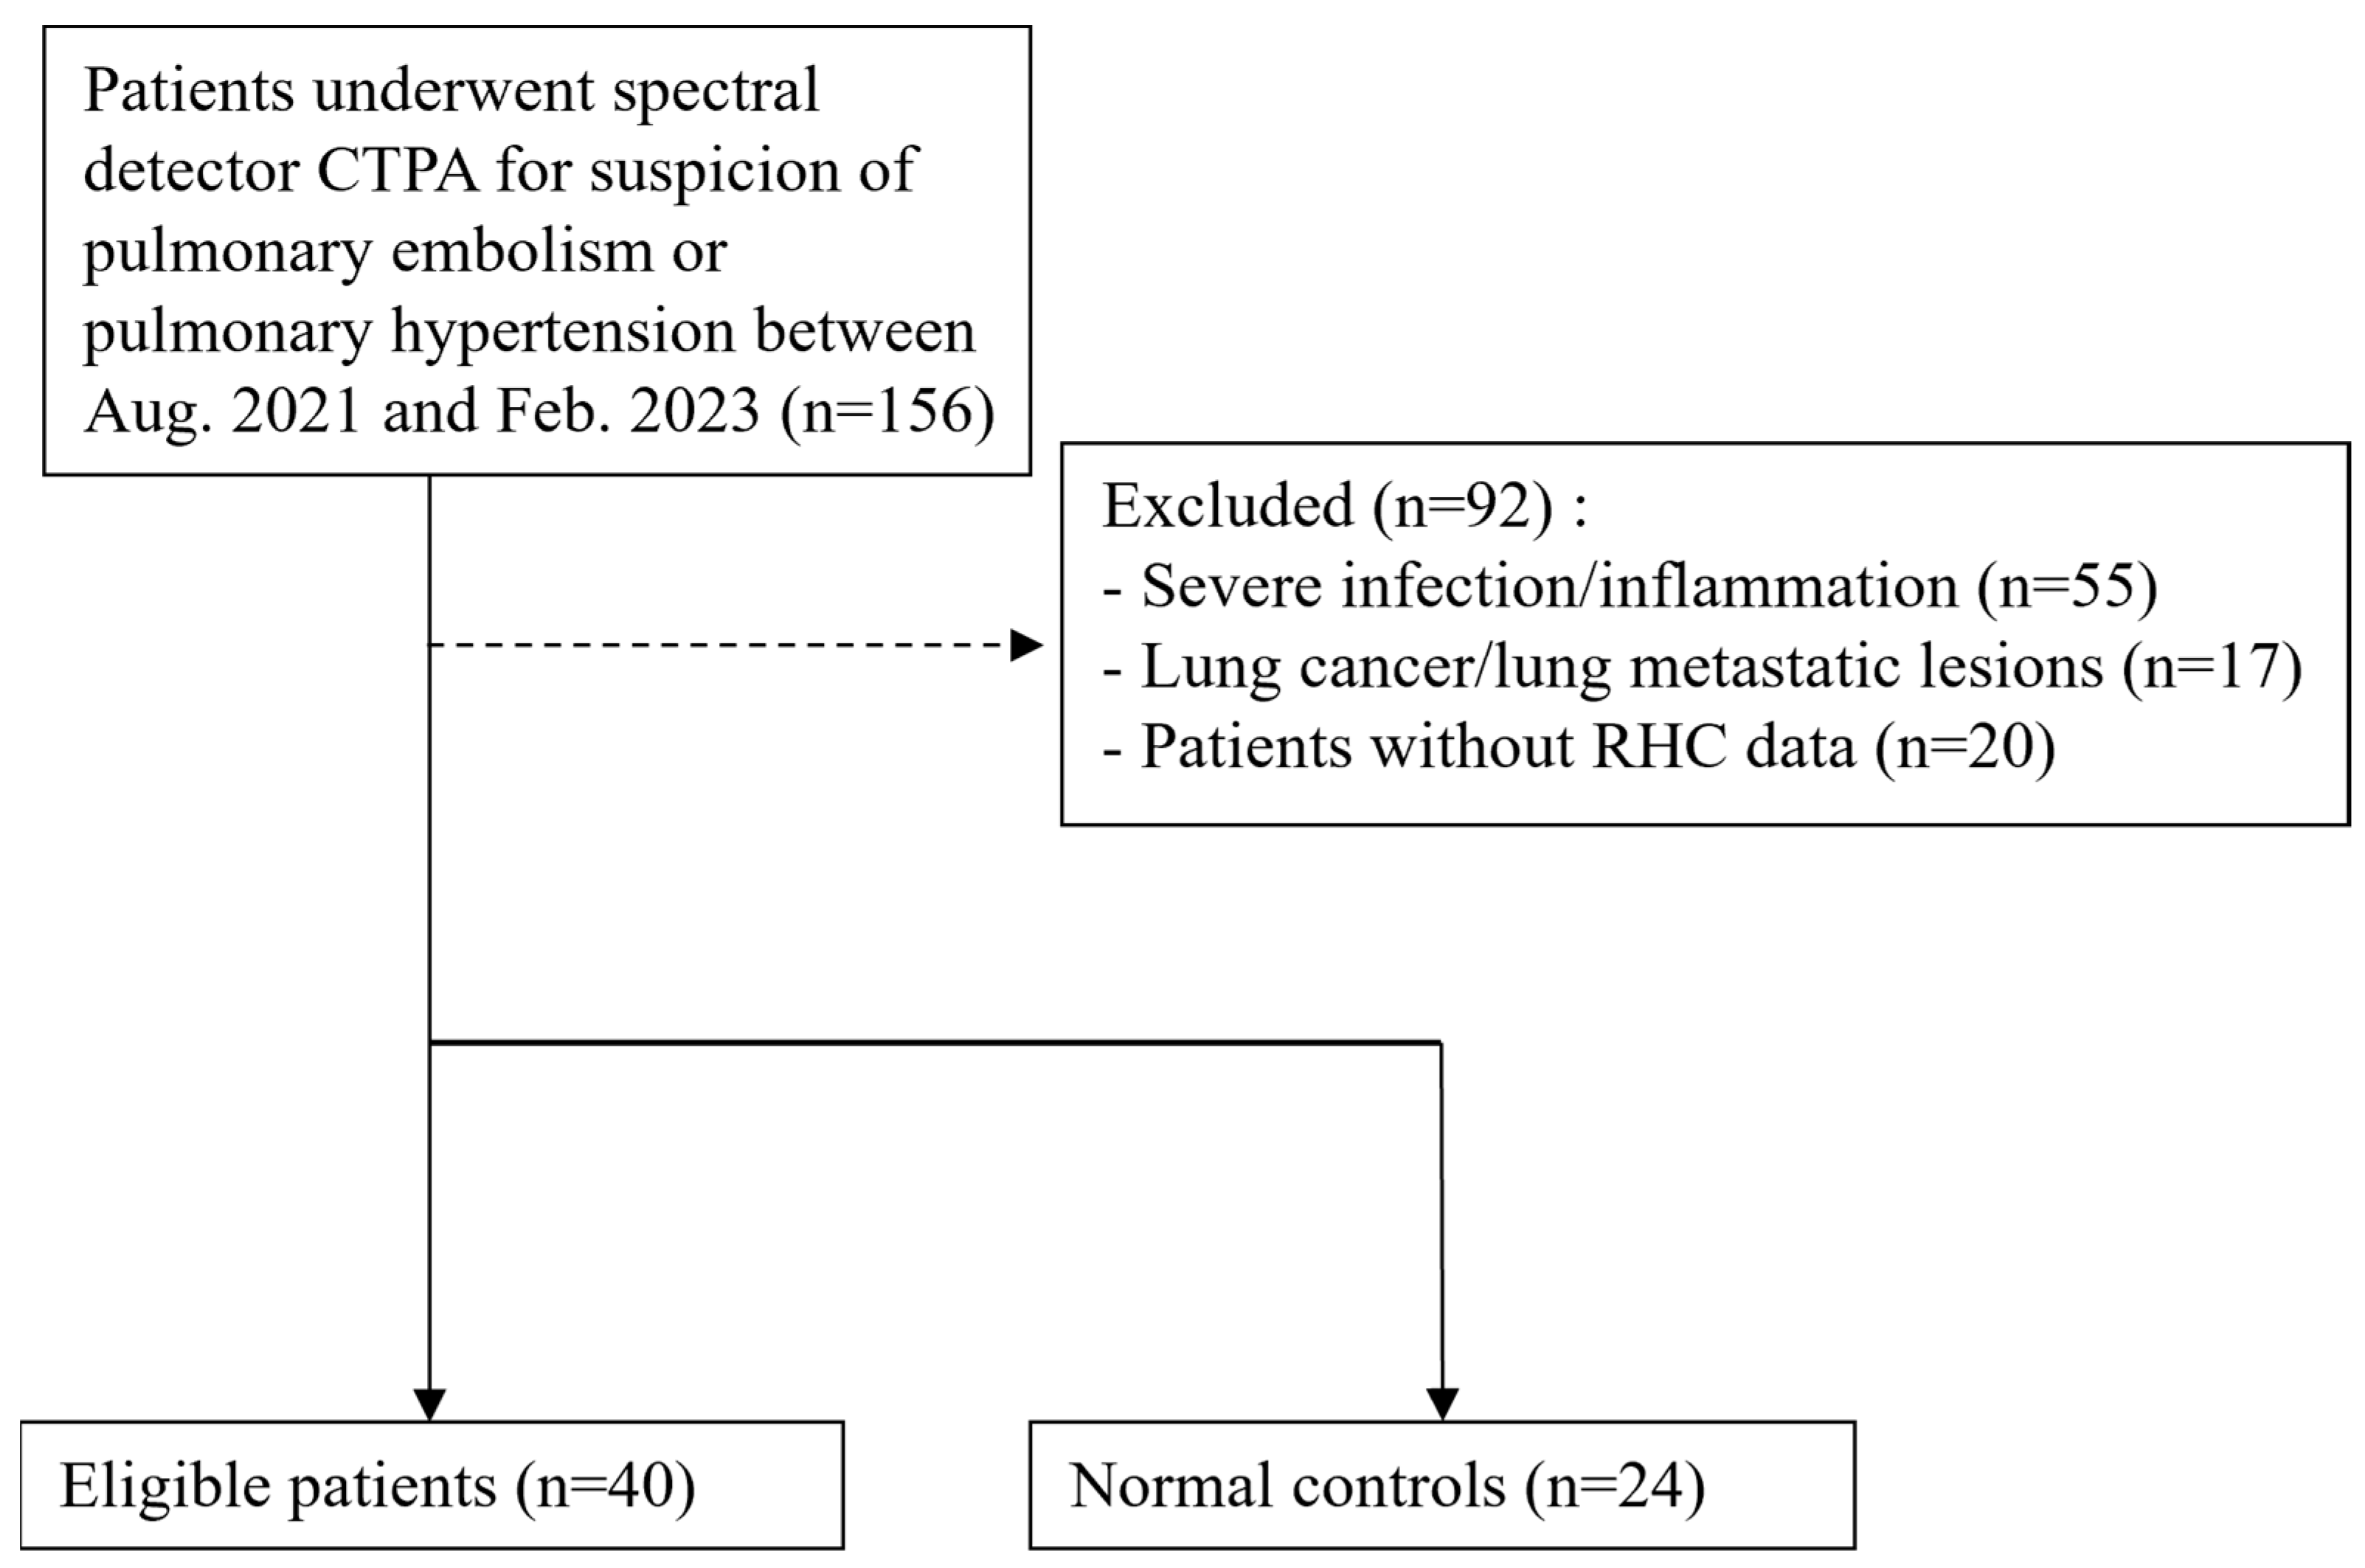

2.1. Patient Population

3.1. Study Population